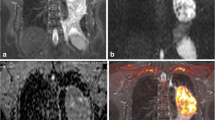

Lung diffusion-weighted magnetic resonance imaging (DWI) has shown a promising value in lung lesion detection, diagnosis, differentiation, and staging. However, the respiratory and cardiac motion, blood flow, and lung hysteresis may contribute to the blurring, resulting in unclear lung images. The image blurring could adversely affect diagnosis performance. The purpose of this study is to reduce the DWI blurring and assess its positive effect on diagnosis. The retrospective study includes 71 patients. In this paper, a motion correction and noise removal method using low-rank decomposition is proposed, which can reduce the DWI blurring by exploit the spatiotemporal continuity sequences. The deblurring performances are evaluated by qualitative and quantitative assessment, and the performance of diagnosis of lung cancer is measured by area under curve (AUC). In the view of the qualitative assessment, the deformation of the lung mass is reduced, and the blurring of the lung tumor edge is alleviated. Noise in the apparent diffusion coefficient (ADC) map is greatly reduced. For quantitative assessment, mutual information (MI) and Pearson correlation coefficient (Pearson-Coff) are 1.30 and 0.82 before the decomposition and 1.40 and 0.85 after the decomposition. Both the difference in MI and Pearson-Coff are statistically significant (p < 0.05). For the positive effect of deblurring on diagnosis of lung cancer, the AUC was improved from 0.731 to 0.841 using three-fold cross validation. We conclude that the low-rank matrix decomposition method is promising in reducing the errors in DWI lung images caused by noise and artifacts and improving diagnostics. Further investigations are warranted to understand the full utilities of the low-rank decomposition on lung DWI images.

Graphical abstract